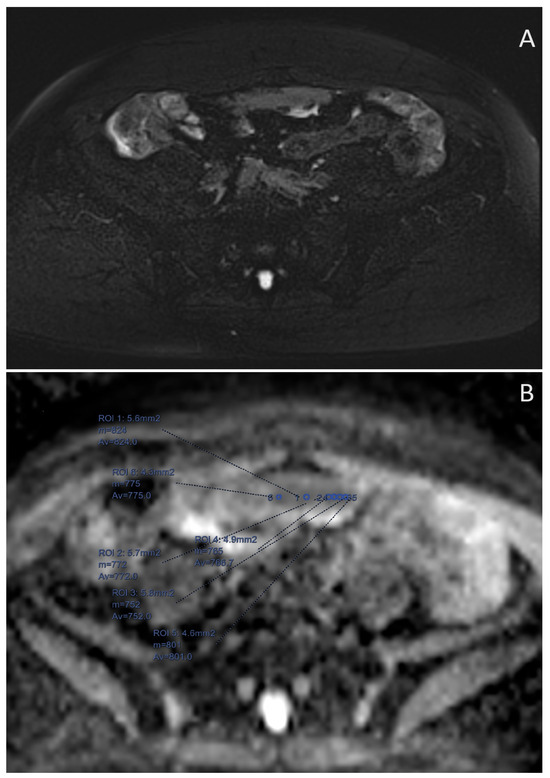

- Derlatka, P.; Grabowska-Derlatka, L.; Halaburda-Rola, M.; Szeszkowski, W.; Czajkowski, K. The Value of Magnetic Resonance Diffusion-Weighted Imaging and Dynamic Contrast Enhancement in the Diagnosis and Prognosis of Treatment Response in Patients with Epithelial Serous Ovarian Cancer. Cancers 2022, 14, 2464. [Google Scholar] [CrossRef]